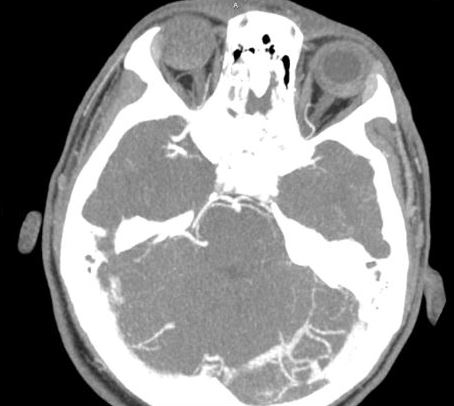

A 15 yo M presents to the ED with headache x 3 days. He reports associated nausea, vomiting x 3. He denies past medical history and has never had a similar headache. His sister does have a history of protein S deficiency. On exam, he is uncomfortable appearing and does have photophobia. He has no neurologic deficits. A CT head without contrast is normal. A CT venogram is performed and shown below. What's the diagnosis? (scroll down for answer)

Answer: Left transverse sinus thrombosis

Central Venous Thrombosis

- Presents with diffuse headache that may be sudden in onset or progressive

- Impaired venous drainage --> increased ICP

- Venous occlusion --> ischemia, infarction, hemorrhage --> focal neurologic deficits or seizure

- Associated with hypercoagulable states

- Recent surgery, estrogen use, factor V Leiden, pregnancy/postpartum, and hypercoagulability diseases such as protein S deficiency

- Diagnosis

- Elevated opening pressure on LP

- CTV or MRV (definitive)

- Treatment

- Anticoagulation

- Thrombolysis or thrombectomy may be considered